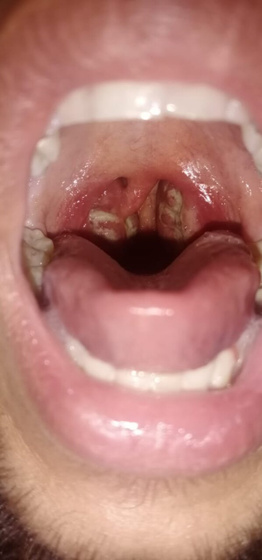

Брат вчера чувствовал себя не очень. С утра мерз но не стал обращать внимание. К обеду поднялась температура 37.5 и горло болело немного. Но под вечер глаза красные и температура 38.3. Посмотрела горло, ужас, я такое в первый раз вижу за всю жизнь. Что это? Может кто знает

Это гнойная ангина, помогут только антибиотики и полоскание

Гнойная ангина! Врача срочно, он назначит антибиотики (без них эта дрянь не проходит, и температура не спадёт пока пробки белые не выйдут) пока парацетамол от температуры и горло каждый час хлоргекседином полоскать!

Лакунарная. *

Лакулярная ангина. Лечим старшему суммамедом( антибиотик), спреи в горло, обильное питьё, жаропонижающие. Тоже ей страдала с 16-23 года примерно. И старший тоже сейчас часто болеет

Фолликулярная ангина у меня похоже выглядела. Адская боль в горле, температура 40

Это тонзиллит (ангина). К доку и срочно.